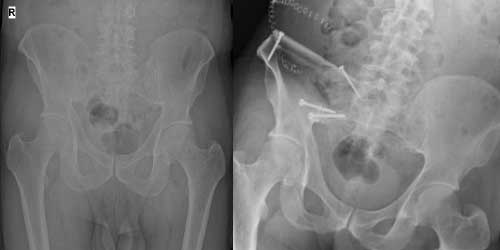

Omurga metastazı, kanserin ilk olarak iç organlarda gelişip daha sonra omurga kemiklerine yayılması sonucu oluşan bir durumdur. Çoğunlukla kan yoluyla sıçrayan bu tür metastaz, hastalarda sırt ve bel ağrısı gibi şikayetlerle kendini gösterir. Erken teşhis ve uygun tedavi yöntemleri, hastaların yaşam kalitesini artırmada kritik bir rol oynar.

Tedavide başarıyı artıran en önemli etkenlerden biri ameliyat öncesi iyi bir hazırlık ve cerrahi planlama yapmaktır. Her şeyden önce tanı doğru konmalı. Bunun için hasta iyi dinlenip, detaylı muayene edildikten sonra tetkikleri dikkatli incelenmelidir.